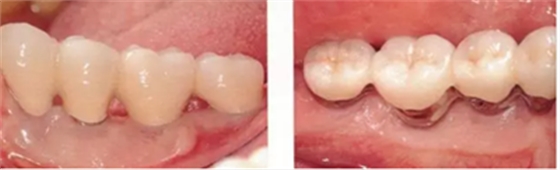

▲圖10-11,12

佩戴最終修復體后2年的狀態(tài)。頰舌側角化齦寬度均充足。

▲圖10-13,14

圖10-13 佩戴最終修復體后16年的狀態(tài)。

圖10-14 同時期的(牙合)面照。